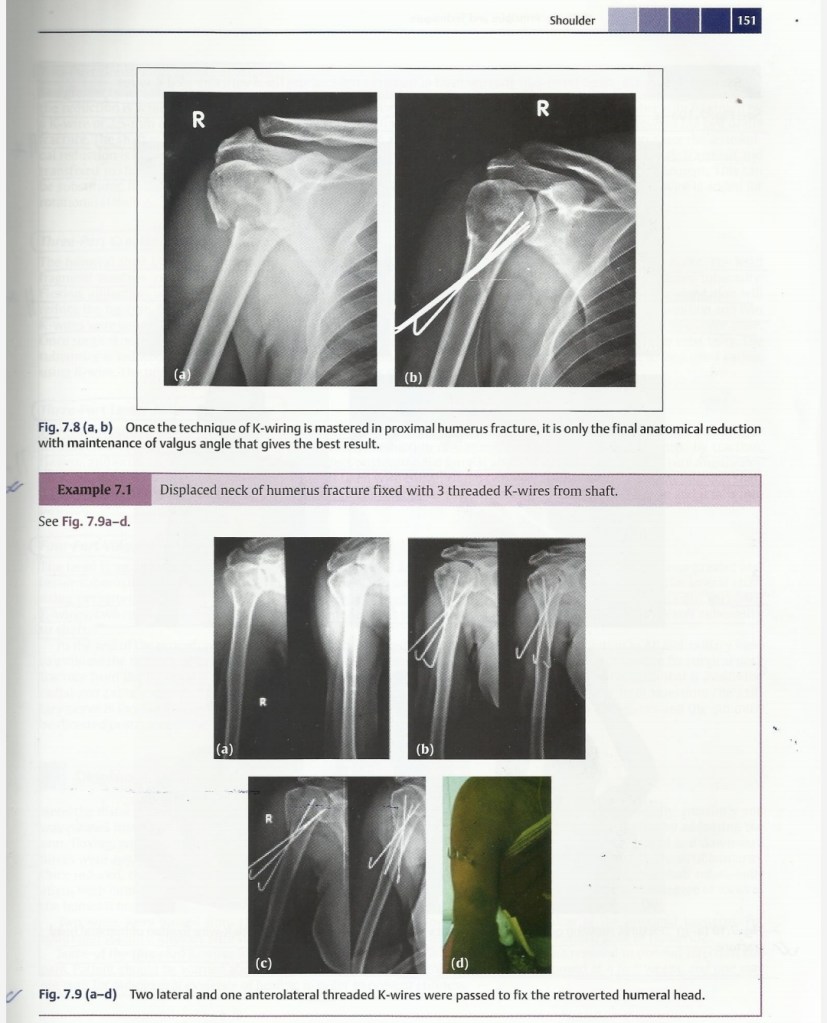

Lecture Pediatric Orthopedic injuries